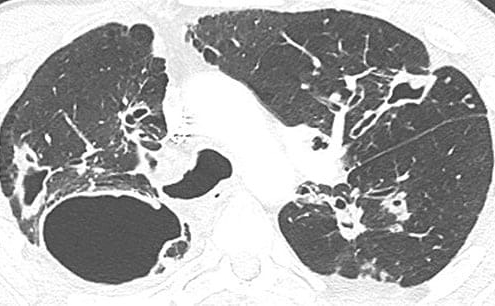

Визуализация и диагностика неинвазивного аспергиллеза с помощью КТ

Раздел: Необычные решения